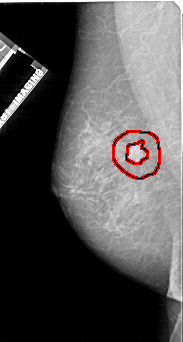

FILE: A_1112_1.LEFT_MLO.OVERLAY

TOTAL_ABNORMALITIES 1

ABNORMALITY 1

LESION_TYPE MASS SHAPE IRREGULAR MARGINS SPICULATED

ASSESSMENT 5

SUBTLETY 5

PATHOLOGY MALIGNANT

TOTAL_OUTLINES 2

BOUNDARY

CORE